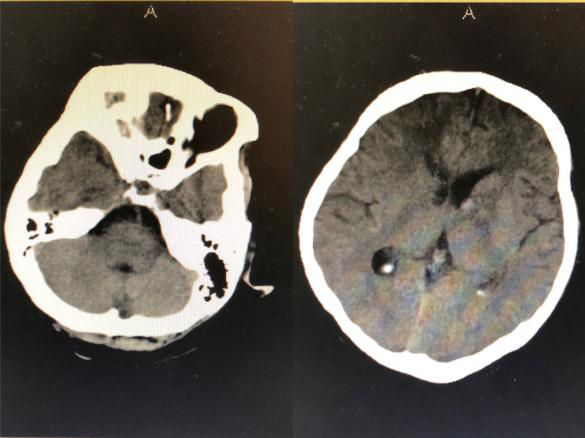

2018年9月3日,一位突发昏迷的患者被推到了神经外科病区。头颅CT提示脑出血破入脑室,合并急性脑积水,必须立即手术。当医生和患者家属提到手术时候,患者家属确实欲言又止,犹豫不决,询问患者家属后得知患者父母已故,也没有子女,唯一的亲人就是姐姐,患者与姐姐都没有工作,仅靠着姐姐的低保维持生活,如今听到要手术,姐姐不知如何是好。时间不等人,如果再拖延时间患者可能因急性脑积水失去生命,神经外科王刚副主任告诉患者家属先做手术抢救生命,钱以后再说,手术顺利进行,术后患者转入重症监护室。

得知患者经济困难后,崔健科主任积极与医院沟通,当大家来到患者仅有几平方米的“家”中,看到他们极其贫困的生活状况时,不由得潸然而泪,决定帮助患者渡过难关。主动与患者家属联系,告知他们安心看病,生命永远是第一位的。经过22个日日夜夜与死神博弈,在神经外科团队的全力救治及精心护理下,患者逐渐意识转清,一侧的肢体力量逐渐恢复,并于10月10日步行出院。